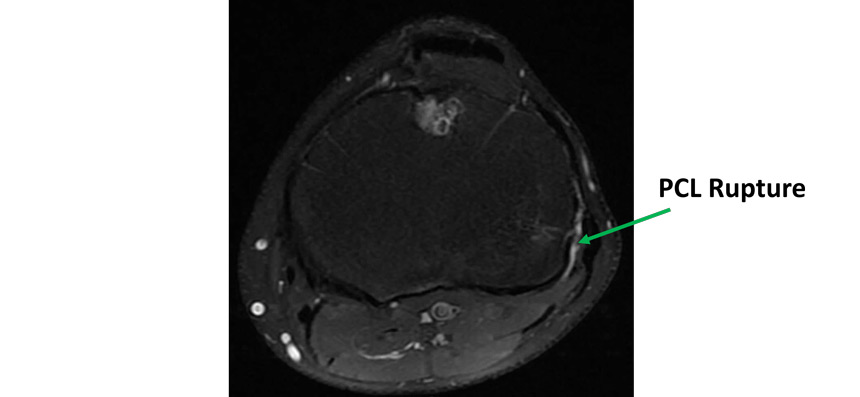

Pre operative MRI

- Knee MRI Findings:

- Rupture of the PCL, PLC and LCL

- Intact ACL

- No meniscal tear

- No cartilage injury